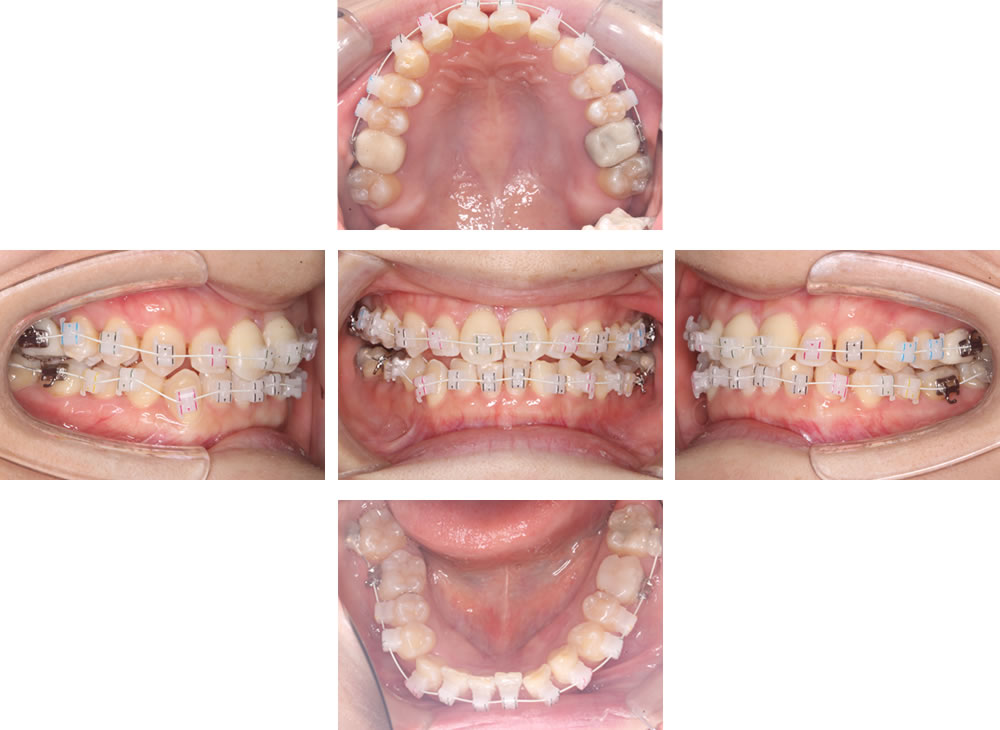

ホワイトブラケットにより3次元矯正

拡大終了後は、ホワイトブラケットを用いて三次元的な矯正治療を行います。ブラケットに付いている色は装着位置を見分けるためのもので、時間の経過とともに自然に消えます。